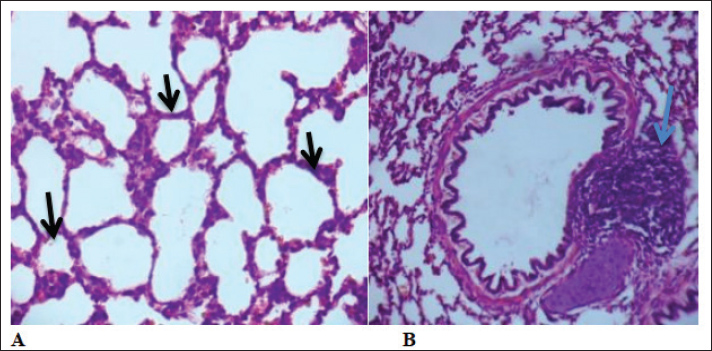

The Vitek2 system provided reliable identification (93% probability), supporting the accuracy of the isolates used in this study. The antimicrobial susceptibility profile revealed varying resistance patterns, which may have clinical implications for treatment strategies. Further studies are needed to explore the virulence mechanisms and potential zoonotic risks associated with Raoultella planticola. Histopathological resultsHistological examination of lung tissue revealed emphysema and atelectasis (Fig. 6A and B). Emphysema was characterized by permanent enlargement of air spaces distal to the terminal bronchioles, accompanied by destruction of alveolar walls without significant fibrosis.

Fig. 6. Group of infected rabbits lung (A) Bronchiols show emphysema aggregation of lymphocytic cell (black arrow)( B) show emphysema structure atelectasis (black arrow) H&E stain 400X and lung H&E stain 200X. Gross examination of sacrificed animals (group of infected rabbits) showed hemorrhage in the upper respiratory tract (Fig. 3). The trachea exhibited a semi-circular hyaline cartilage structure (Fig. 4), and the bronchi branched into left and right bronchioles, consistent with typical mammalian respiratory anatomy. Normal histological details of trachea of control group• Tunica mucosa • Tunica submucosa • Tunica adventitia • C-shaped hyaline cartilage (Fig. 5A) • score lesion of Pathological Changes • Emphysema was observed in 3 out of 5 cases (60%) (Fig. 4). • No pathological changes were seen in 2 cases (40%). • Vascular changes, including congestion, thrombosis, and alveolar hemorrhage, were noted in 10% of affected cases. Comparative morphologyLight microscopy analysis confirmed Gram-negative rods for Raoultella planticola. However, differentiation from Klebsiella spp. was challenging due to morphological similarities (Fig. 2A and B). The histological findings of emphysema and atelectasis align with Blagojević et al. (2018), who described similar structural changes in respiratory infections. The observed hemorrhage and vascular congestion support Castro et al. (2001), who linked these changes to bacterial-induced trauma. The 60% incidence of emphysema suggests that Raoultella planticola primarily induces chronic obstructive pulmonary disease (COPD)-like lesions, differing from Sarhad (2011), who reported fibrinous pleuropneumonia as the dominant pathology. This discrepancy may stem from differences in infection routes or host susceptibility. The short respiratory passage and direct bronchial branching in rabbits (Abdelsalam and Al Sadrani, 2015) likely contribute to higher lung infection rates. Additionally, the similarity between Raoultella and Klebsiella (Alampoondi Venkataramanan et al., 2021) complicates microscopic differentiation, necessitating advanced diagnostic methods like Vitek2.Contrary to Vinshia, J. J., (2024), this study found no fibrinous bronchopneumonia, instead emphasizing edema and congestion (Das and Bhagman, 1997). The reclassification of Raoultella from Klebsiella prior to 2001 further underscores the need for precise microbiological identification (Fig. 8). This study highlights Raoultella planticola's potential to cause respiratory pathology, warranting further investigation into its zoonotic risks.

Fig. 7. The lung is show emphysema group of infected rabbits show moderate fibroplasia of arterioles. (black arrow) and tertiary bronchioles (blue arrow). H&E stain 400X (Castro et al., 2001).

Fig. 8. Group of infected rabbits show(A) arterioles moerate perivascular mononuclear cells infiltration with evidence of vasculitis (black arrow) H&E stain 400X. and B show tertiary bronchioles (blue arrow)with dilated pulmonary arterioles(red arrow) and the lung is show emphysema. H&E stain 100X. DiscussionThis comprehensive examination reveals that when rabbits were given intranasal doses of Raoultella planticola, it led to a mild yet noticeable respiratory infection. The evidence is clear—clinical signs such as dullness, nasal discharge, and watery eyes were apparent. What's more, significant pathological changes were observed, particularly in the lungs, with pulmonary emphysema and atelectasis appearing in 60% of the cases examined. Add to that the striking visible signs of hemorrhage, and it paints quite a concerning picture of the infection's impact. The bacterium's ability to cause disease, boosted by its protective polysaccharide capsule and its close resemblance to Klebsiella species, was convincingly verified using the VITEK2 system. However, when we dive into the histopathological findings, we see hints of emphysema and some intriguing vascular changes that resonate with certain literature; yet, there’s a twist—this evidence points more toward a COPD-like condition rather than the fibrinous pneumonia that's been noted in other studies. Moreover, the antimicrobial susceptibility profile painted a complex picture, revealing varying degrees of resistance that certainly pose difficulties for treatment. All in all, these findings affirm that R. planticola can trigger respiratory issues through the nasal route, shedding light on the pressing need for accurate diagnostics and further exploration into its virulence and potential to jump from animals to humans. ConclusionRaoultella planticola are very similar in phenotype to Klebsiella spp. in epidemiology and the clinical signs in respiratory infection of rabbit. The R. planticola causes mild to moderate emphysema in local rabbit. The previous difficulties in the identification of R.planticola and known of more detailed may needed PCR technique to confirm diagnosis. Intranasal infection was the effective route and the main pathological changes observed in the respiratory system characterized by presence of atelectasis indicated of emphysema. Further studies of molecular sequences are required. AcknowledgmentsThe authors extend their sincere thanks to the Faculty of Veterinary Medicine/the University of Kufa for their unwavering support. The authors also intensely appreciate the contributions of the veterinarians and staff at the Veterinary Hospital Laboratory and Wasit Abattoir for their technical support and collaboration in sample collection and analysis. Authors' ContributionAll listed authors have made significant intellectual and academic contributions to this study. Each author has reviewed and approved the final manuscript for publication. Competing interestsThere are no conflicts of interest numerous of the authors concerning the publishing this manuscript. FundingNone. Data availabilityAll the datasets formed or examined during this work are included in the publication. ReferenceAbdelsalam, E.B. and Al Sadrani, A.A. 2015. Incidental findings of pathological significance in pneumonic lungs of sheep in Al Qassim Area, Kingdom of Saudi Arabia: an abattoir survey. Comparative. Clin. Pathol. 24, 951–955. Alampoondi Venkataramanan, S.V., George, L., Sahu, K.K. and Abraham, G.M. 2021. A 5-Year Retrospective analysis of Raoultella planticola bacteriuria. InfectDrug. Resist. 1989, 1989–2001. Bagley, S.T., Seidler, R.J. and Brenner, D.J. 1981. Klebsiella planticola sp. nov.: a new species of Enterobacteriaceae found primarily in nonclinical environments. Curr. Microbiol. 6(6), 105–109. Bancroft, J.D., Layton, C. and Suvarna, S.K. 2013. Bancroft's theory and practice of histological techniques. Churchill Livingstone Elsevier. Nottingham, UK: Elsevier. Blagojević, M., Božičković, I., Ušćebrka, G., Lozanče, O., Đorđević, M., Zorić, Z. and Nešić, I. 2018. Anatomical and histological characteristics of the lungs in the ground squirrel (Spermophilus citellus). Acta Veterinaria Hungarica 66(2), 165–176. Castro, P., Chiu, P., Kremenek, T. and Muntz, R. A probabilistic room location service for wireless networked environments. In Ubicomp 2001: Ubiquitous Computing: International Conference Atlanta Georgia, USA, September 30–October 2, 2001 Proceedings 3,2001 Springer Berlin Heidelberg, Atlanta, Georgia, 3, pp 18–34. Chun, S., Yun, J.W., Huh, H.J. and Lee, N.Y. 2014. Low virulence? Clinical characteristics of Raoultella planticola bacteremia. Infection 42, 899–904. Das, B., Rao, A.R. and Madhubala, R. 1997. Difluoromethylornithine antagonizes taxol cytotoxicity in MCF-7 human breast cancer cells. Oncol. Res. Featuring. PreClin. Clin. Cancer. Therapeutics. 9(11-12), 565–572. Demiray, T., Koroglu, M., Ozbek, A. and Altindis, M. 2017. A rare cause of infection, Raoultella planticola: emerging threat and new reservoir for carbapenem resistance. Infection 44, 713–717. enters for Disease Control and Prevention. (2010). Klebsiella pneumoniae in healthcare settings. Available via https://www. cdc. gov/hai/organisms/klebsiella/klebsiella. html (accessed: 2019, May 20). Eroschenko, V.P. and Di Fiore, M.S. 2013. DiFiore's atlas of histology with functional correlations. Philadelphia, PA: Lippincott Williams & Wilkins, pp: 263–6. Freney, J., Fleurette, J., Gruer, L. D., Desmonceaux, M., Gavini, F., and Leclerc, H. 1984. Klebsiella trevisanii colonisation and septicaemia. Georgi. and Anderson. 1975. The Cornell Veterinarian. Cornell Vet. 66, 309–323. Ghoshal, N.G. and Bal, H.S. 1989. Comparative morphology of the stomach of some laboratory mammals. Lab. Animals 23(1), 21–29. Harcourt-Brown, F. 2002. Textbook of rabbit medicine. Elsevier Health Sciences.. Howell, C. and Fakhoury, J. 2017. A case of Raoultella planticola causing a urinary tract infection in a pediatric patient. Translational Pediatrics 6(2), 102. Jiménez Castro, D., Pérez-Rodríguez, E., Montaner, L., Flores, J. and Díaz Nuevo, G. 2001. Diagnostic value of D dimer in pulmonary embolism and pneumonia. Respiration 68(4), 371–375. Luna, L.G. 1968. Manual of histologic staining methods of the Armed Forces Institute of Pathology. In Manual of histologic staining methods of the Armed Forces Institute of Pathology. McGraw-Hill, New York: NY, pp: xii–258. Podschun, R., Acktun, H., Okpara, J., Linderkamp, O., Ullmann, U. and Borneff-Lipp, M. 1998. Isolation of Klebsiella planticola from newborns in a neonatal ward. J. Clin. Microbiol. 36(8), 2331–2332. Ramchandani, V.A., Bosron, W.F. and Li, T.K. 2001. Research advances in ethanol metabolism. Pathologie. Biologie. 49(9), 676–682. Sahu, K., Sherif, A. and Davaro, R. 2020. A rare cause of cellulitis: photobacterium damselae. J. Microsc. Ultrastructure 8(1), 25–26. Sarhad, A.N.S. 2011. Pathogenesis of Pasteurella multocida in Rabbits by Intra-nasal and Intra-ocular infection. Iraqi. J. Vet. Med. 35(1), 42–53. Sękowska, A. 2017. Raoultella spp.—clinical significance, infections and susceptibility to antibiotics. Folia. Microbiologica. 62(3), 221–227. Suvarna, S.K., Layton, C. and Bancroft, J.D. 2019. Theory and practice of histological techniqueseighth. Oxford, UK: Elsevier Health Sci. Vinshia, J.J., Padmavathy, K. and Sathyapriya, B. 2024. Comparison of the VITEK® 2 system with conventional methods for species identification and antimicrobial susceptibility pattern of staphylococcal carrier isolates. Int. Res. J. Multidisciplinary. Scope. (IRJMS). 5(2), 940–948. Woodman, C.B., Collins, S., Winter, H., Bailey, A., Ellis, J., Prior, P., Yates, M., Rollason, T.P. and Young, L.S. 2001. Natural history of cervical human papillomavirus infection in young women: a longitudinal cohort study. Lancet 357(9271), 1831–1836. | ||